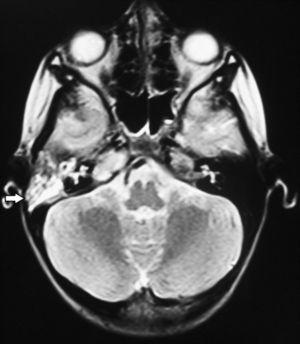

Se realiza una resonancia magnética cerebral, donde se observa ocupación del oído medio y celdillas mastoideas derechas, con compromiso del ápice del peñasco (fig. 3).